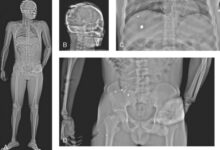

- Imaging in Trauma patients (You Have No Time)